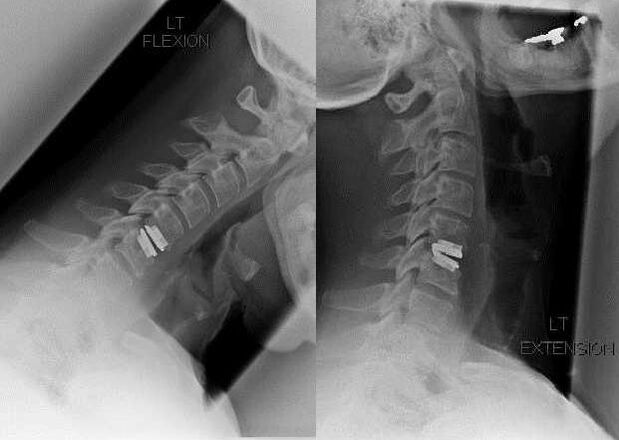

Le indicazioni per l'intervento chirurgico comprendono l'inefficacia del trattamento conservativo e le complicanze dell'osteocondrosi cervicale, ad esempio la mielopatia discogenica, la sindrome dell'arteria vertebrale e la sindrome radicolare. Per alleviare il carico sul midollo spinale, sui vasi sanguigni e sulle radici spinali, vengono eseguite le seguenti operazioni:

- laminectomia;

- laminotomia;

- foraminotomia;

- faccetectomia;

- Discectomia.

Durante l'intervento chirurgico è possibile asportare frammenti ossei e legamenti e rimuovere completamente o parzialmente i dischi intervertebrali. Per le piccole sporgenze erniarie viene spesso eseguita la vaporizzazione laser del nucleo del disco.

Dopo la rimozione delle strutture vertebrali, è spesso necessaria la stabilizzazione dei segmenti motori della colonna vertebrale attraverso la fusione spinale o l'installazione di autoinnesti ossei e cutanei.